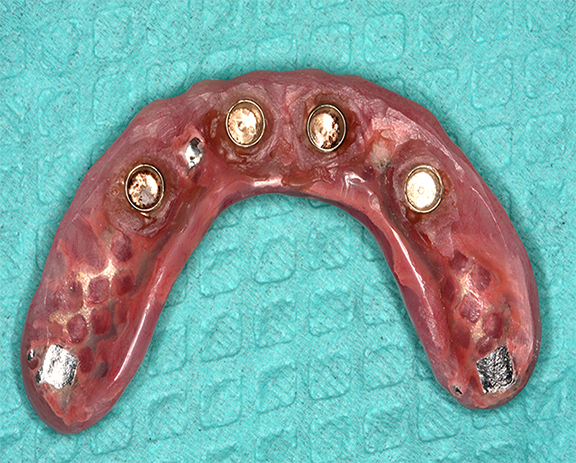

To adequately relieve the denture in the area of the implants, an impression and bite registration material was placed on the intaglio surface of the prosthesis, and then the prosthesis was placed over the overdenture abutments.41 The prosthesis was removed from the mouth after the polymerization of the impression material. The indentations of the denture caps were registered in the impression material (Figure 13). A vent hole bur was used to drill straight through the center of the indentations (Figure 14, top).41 A recess bur that fitted right in the hole was used to open the spaces (Figure 14, bottom). Next, retention was created by using an inverted cone retention bur.41 Then a round bur, football-shaped bur, and polisher were used to finish and polish the recesses.41

Block-out rings were placed around the denture caps in the mouth (Figure 15), and more than one was used where required. Block-out rings are used to block out the undercuts between the caps and the tissue and thereby prevent locking of the denture.41 Attachment pickup material was placed around the attachments in the mouth and in the recesses of the prosthesis (Figure 16). The prosthesis was placed in the mouth.41 After the polymerization of the pickup material, the prosthesis was removed from the mouth, finished, and polished.41 The black nylon processing inserts present within the denture caps were removed and replaced with the retentive inserts (Figure 17).41 The amount of retention can be increased by using inserts that provide an added degree of retention, if needed.41

Fig 13. Indentations of abutments registered in the impression material.

Figure 13

Fig 14. Vent holes drilled straight through the center of the indentations (top); recess bur used to open up the space (bottom).

Figure 14

Fig 15. Block-out rings placed to block the undercuts between the denture caps and tissues.

Figure 15

Fig 16. Attachment pickup material was placed around the attachments in the mouth (left) and in the recesses of the prosthesis (right).

Figure 16

Fig 17. Black nylon processing inserts (upper left) were replaced with blue retentive inserts (lower right).

Figure 17